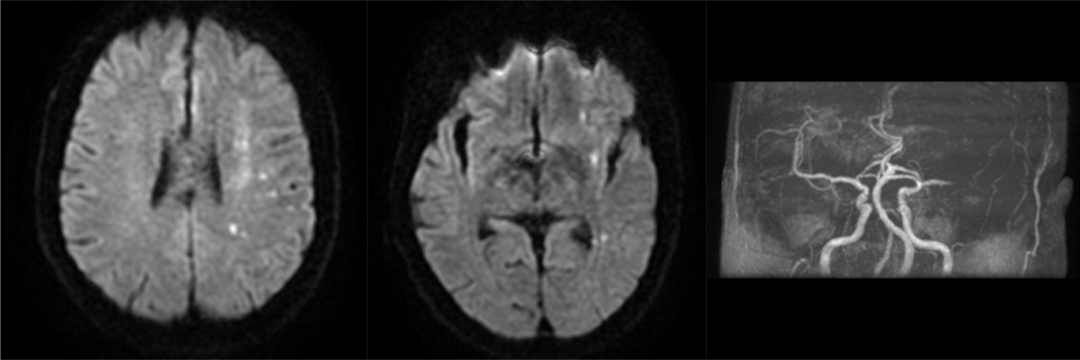

病例2:患者为62岁男性,因右侧肢体无力19小时来诊,既往高血压病史。患者入院后急诊头颅核磁提示左侧半球多发点状梗死灶,左侧大脑中动脉闭塞,NIHSS评分4分。入科后患者病情进行性加重,术前NIHSS评分14分,mRS评分4分,结合患者影像学检查及临床症状符合DAWN(临床-影像不匹配)标准,予急诊血管内介入治疗。

术前核磁影像(左侧半球多发点状梗死灶,左侧大脑中动脉闭塞)